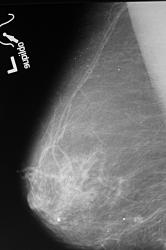

как хорошо виден на прицеле злокачественное узловое образование с микрокальцинатами